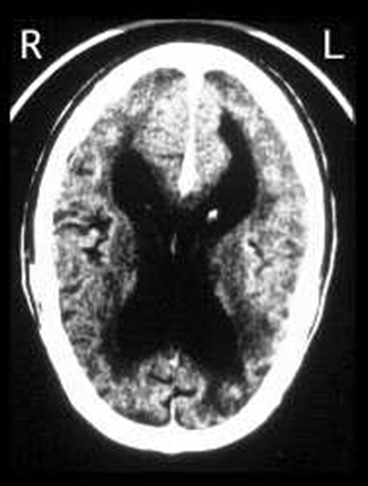

MRI of the brain revealed generalized atrophy, somewhat more prominent in the L > R temporoparietal region, and enlargement of both lateral ventricles. There were minimal scattered T2/FLAIR hyperintensities consistent with microvascular ischemic disease. Laboratory studies for thyroid function and vitamin B12 were normal.

Summary of CT Findings

There is a dramatic loss of parenchyma, manifested here by cortical atrophy and marked enlargement of the lateral ventricles (called hydrocephalus ex vacuo).